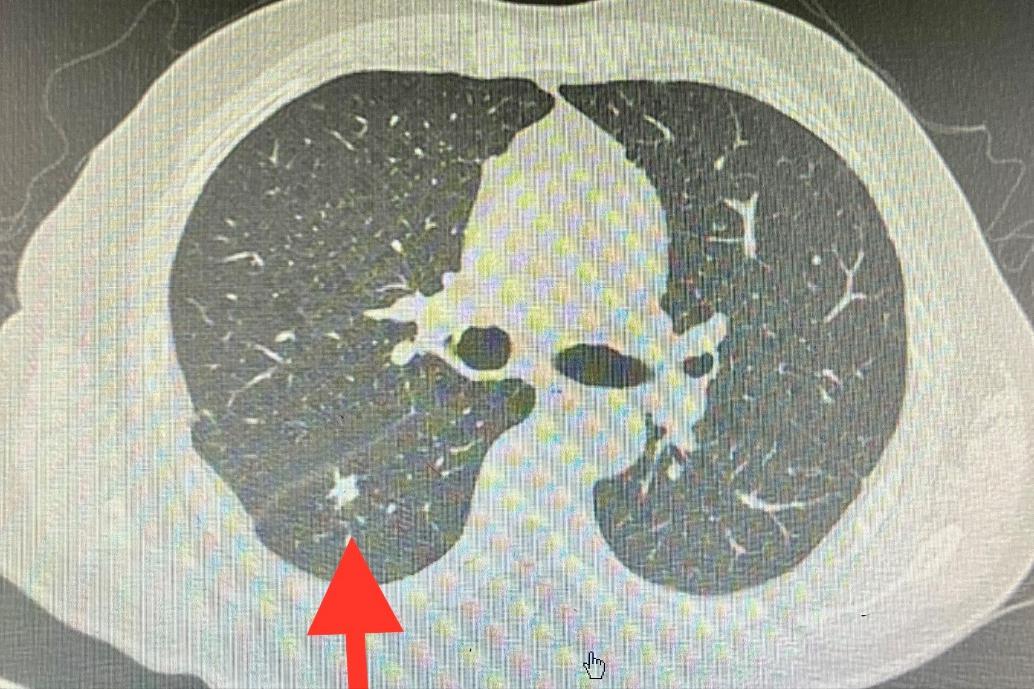

入院后完善检查,胸部CT显示右肺下叶背段实性结节,边缘毛刺,形态不规则,高度考虑恶性病变可能。

⑵看形态:分叶征、毛刺征、血管集束征以及胸膜牵拉征多提示恶性结节。边缘光滑多提示良性结节,如平滑肌瘤、乳头状瘤和结核球等。